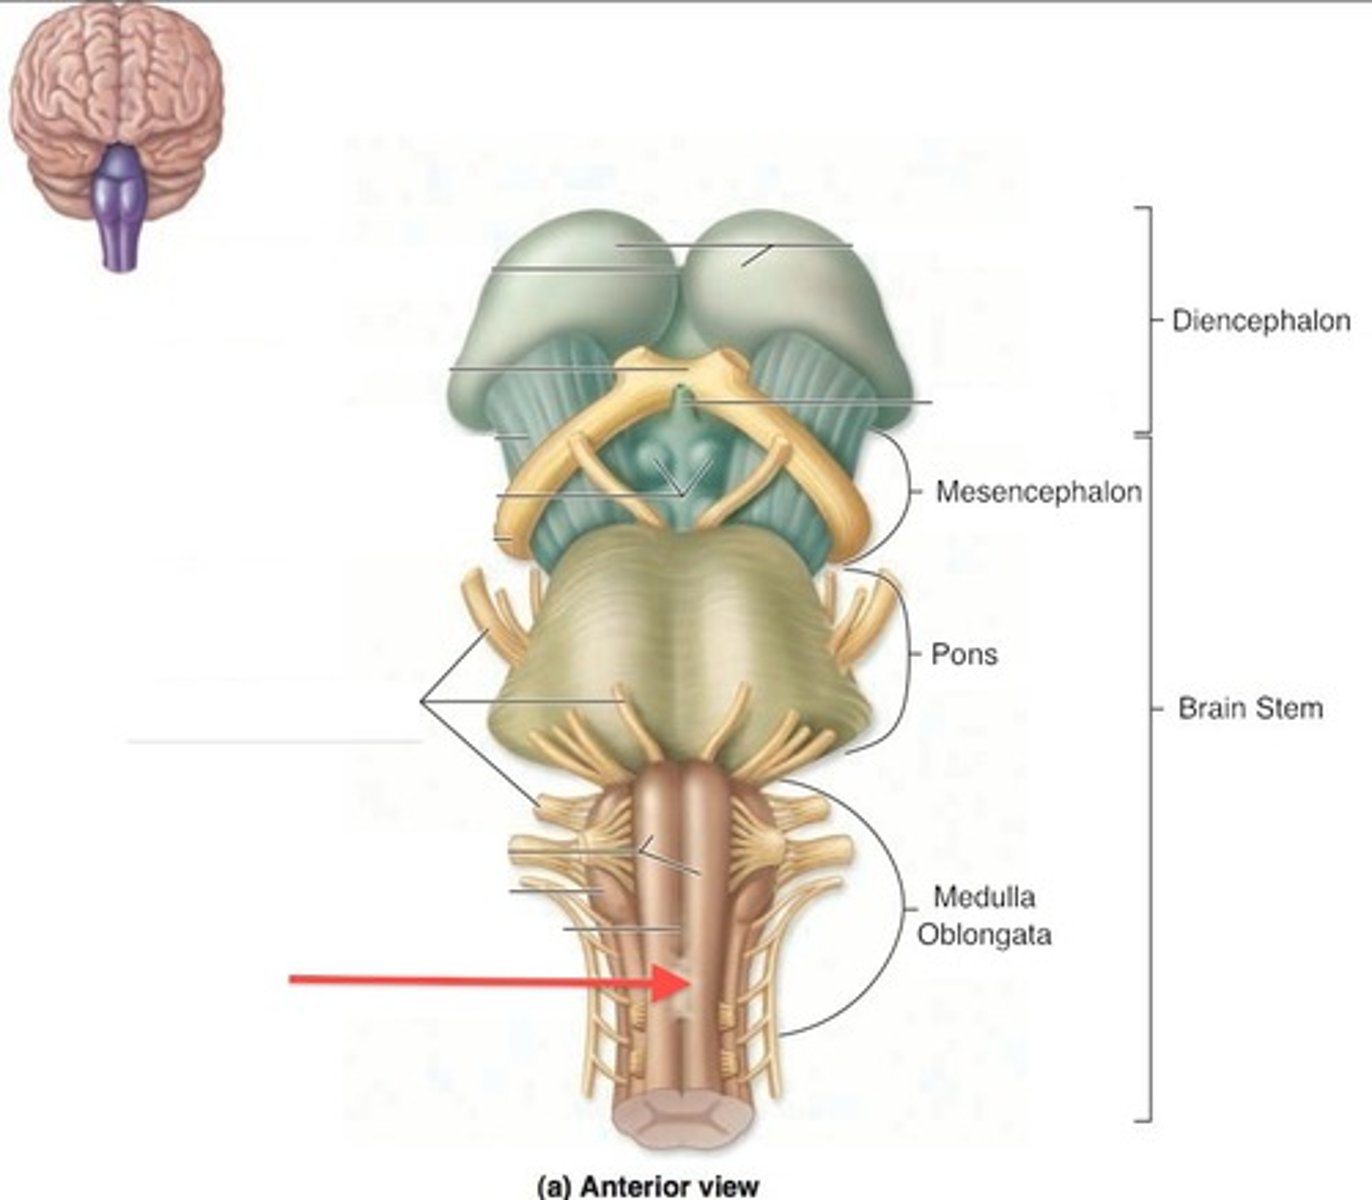

What are the 3 parts of the brain stem?

midbrain, pons, medulla

What is the superior boundary of the medulla?

pontomedullary sulcus

What is the inferior boundary of the medulla?

foramen magnum

What other part of the CNS is the medulla continuous with?

spinal cord

What is the superior boundary of the pons?

isthmus of the brain stem (between pons and cerebral peduncles)

What is the inferior boundary of the pons?

pontomedullary junction

What is the superior boundary of the midbrain?

just under the mamillary bodies of the diencephalon

What is the inferior boundary of the midbrain?

isthmus of brain stem

opening running through the midbrain that separates it into the cerebral peduncles and tectum

cerebral aqueduct (iter or aqueduct of Sylvius)

What does the cerebral aqueduct separate the midbrain into?

cerebral peduncles, tectum

area separating the cerebral peduncles

interpeduncular fossa

Which cranial nerve emerges from the floor of the interpeduncular fossa?

CN III

refers to the ventral part of the cerebral peduncles

columns of white matter that are the corticospinal and corticonuclear (upper motor neuron fibers going to cranial nerve nuclei) running through the midbrain

basis pedunculi (or crus cerebri)

refers to the dorsal part of the cerebral peduncles

tegmentum

part of the midbrain that consists mainly of two (2) pairs of small mounds known collectively as the corpora quadrigemini

tectum

2 pairs of small mounds on the tectum of the midbrain

corpora quadrigemini